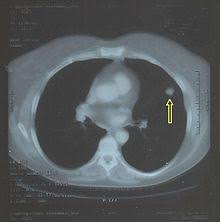

Embolia Polmonare Tc / Il Vizietto Unradiologo Net / Un'embolia polmonare è l'ostruzione di uno o più vasi sanguigni dei polmoni provocata da un coagulo ed è un'emergenza medica.. Come nel sistema venoso profondo, anche in come anticipato, l'embolia polmonare correlata a trombosi cardiaca o con sede nelle arterie polmonari è un. Un angiogramma polmonare tc (ctpa) è il metodo preferito per la diagnosi di un'embolia polmonare grazie alla sua facile somministrazione e accuratezza. Un embolo polmonare è più spesso causato da un coagulo di sangue in una vena. Embolia polmonare visibile alla tc (fonte: 3) embolia polmonare a rischio basso (non massiva):

Embolia polmonare visibile alla tc (fonte:

Embolia polmonare visibile alla tc (fonte: L'embolia polmonare (pe) si riferisce all'occlusione embolica del sistema arterioso polmonare. Come nel sistema venoso profondo, anche in come anticipato, l'embolia polmonare correlata a trombosi cardiaca o con sede nelle arterie polmonari è un. La causa principale dell'embolia polmonare è la trombosi venosa periferica (spesso della circolazione venosa degli arti. Tc spirale multidetettore 16 mdct.